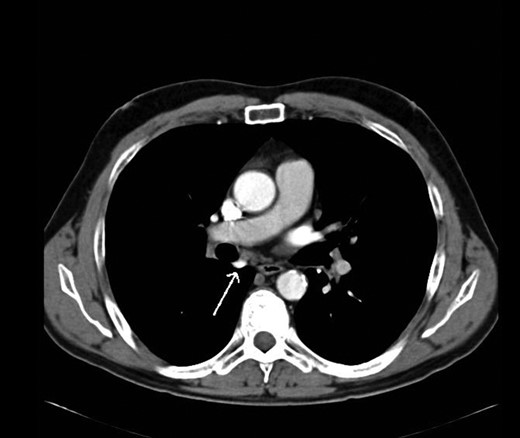

During discussions at the multidisciplinary team meeting, the computed tomography scans of his thorax were reviewed by our radiology colleagues and an anomalous right upper lobe vein was identified.

The patient underwent a right postero-lateral thoracotomy. The right upper lobe pulmonary artery and vein were identified and divided with vascular Endo GIA™ staples. Lymphadenectomy was performed in the draining lymph nodes and we proceeded to isolate the upper lobe bronchus. Prior knowledge of an anomalous venous drainage of the upper lobe made us adopt a cautious approach during dissection posterior to the right upper lobe bronchus and a vascular structure was identified that could be traced in the left atrium; thus, it was found to be an anomalous upper lobe pulmonary vein. The anomalous vein was divided with vascular Endo GIA™ staples. The bronchus was divided with a TA™ stapler.

The patient recovered well postoperatively and was discharged home. Histologically, the patient's tumour stage was pT1aN0 (Figs 1–6).

Kim et al. [2] first reported the contrast-enhanced computed tomography findings of aberrant pulmonary veins, which were observed as a focal nodularity attached to the posterior wall of the bronchus intermedius. Pulmonary vein variations are usually seen in the common pulmonary vein and the middle lobe vein draining into the inferior pulmonary vein or the left atrium [3]. There are only a few CT studies of the upper lobe vein. The frequency is reported between 1.7 and 5.7% [3].

Kim et al. [2] eluded that in 5% of normal subjects, the right superior segmental pulmonary veins had an aberrant course also either to the inferior pulmonary vein or directly to the left atrium. Asai et al. [4] noted that in right lung resection surgeries, there was a 5.7% occurrence of abnormal right upper lobe venous drainage.